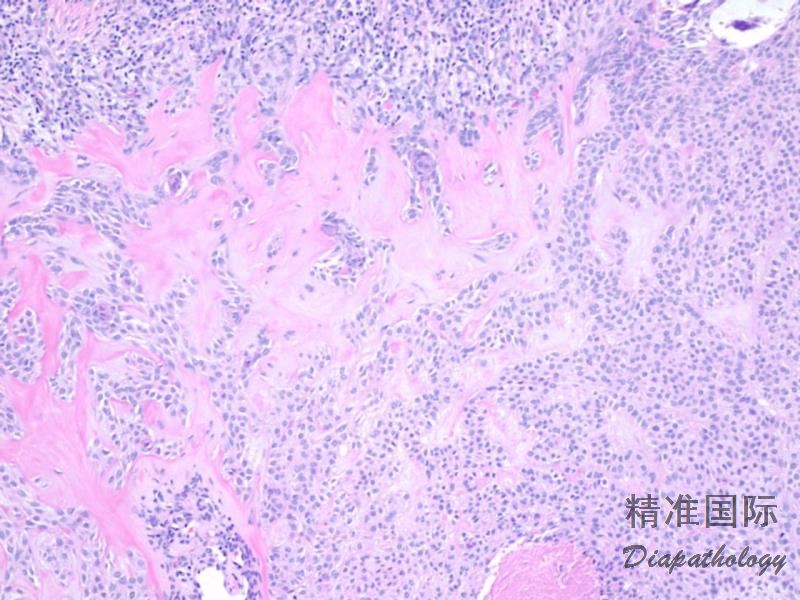

2. 肿瘤以出现细基底样上皮细胞索、角质囊肿和致密的纤维间质三联征为特征;

3. 基底样细胞小。核呈卵圆形,胞浆少,无明显异型性;

5. 间质有大量致密的胶原纤维。